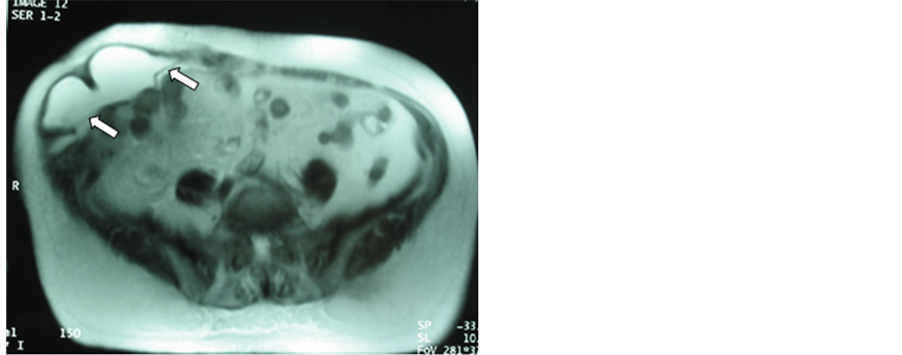

In the postoperative period, the first month control was especially useful to manage the immediate postoperative seroma: position, amount and relation with the mesh. In the axial and sagittal views it is possible to see the seroma between the skin and the mesh, behind the mesh inside the abdominal cavity, or both (Figures 2-4). Also, this approach allows to determinate the correct position of the mesh, the absence of relapsing and the relation with the intestinal content.

Three patients developed big-size seroma (30%) (Figures 2-4), but evacuation was not necessary.

Figure 4. One month postoperative axial MRI control after laparoscopic surgery for a large right-subcostal incisional hernia. The arrows show the mesh and a big seroma under the skin.